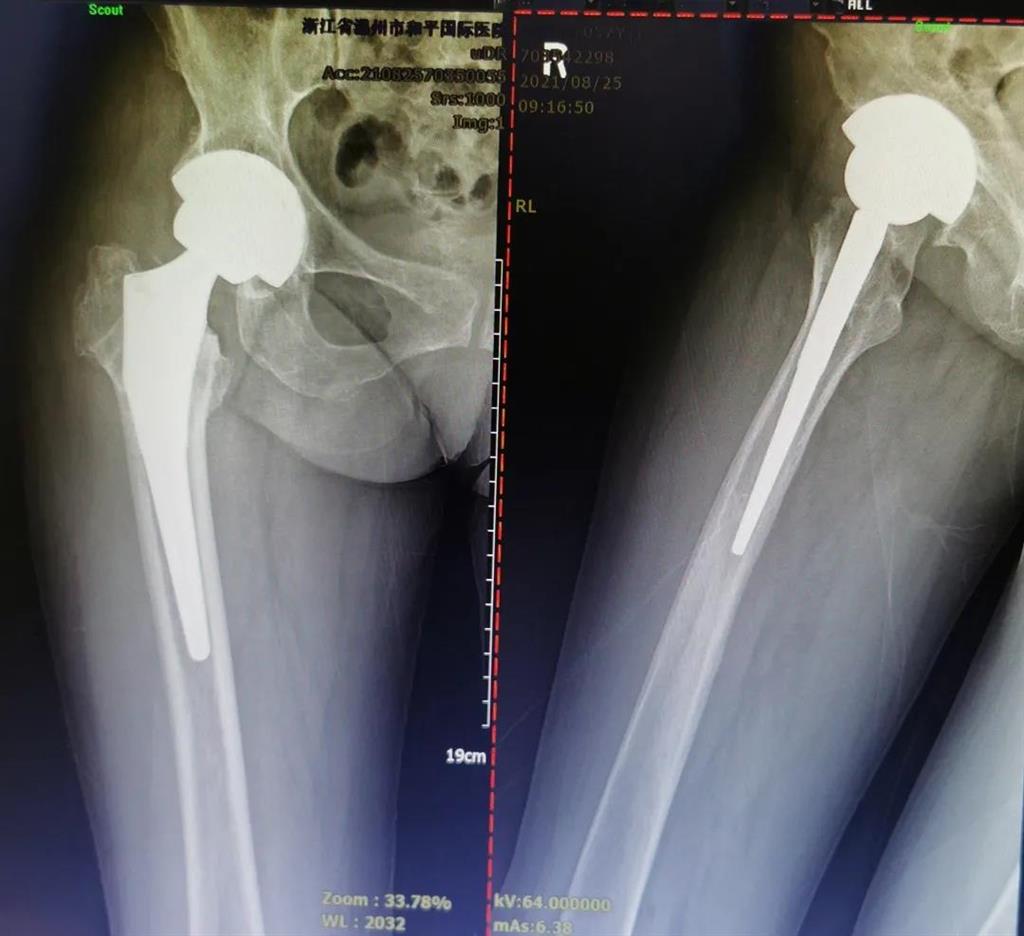

手術(shù)很成功!李女士術(shù)后第二天便可下地進行簡單的鍛煉了。

兩個月后,李女士的腿已與常人無異,苦纏2年有余的病痛,終于徹底消散。

(△做完“右股骨頸全髖關(guān)節(jié)置換術(shù)”后的影像)